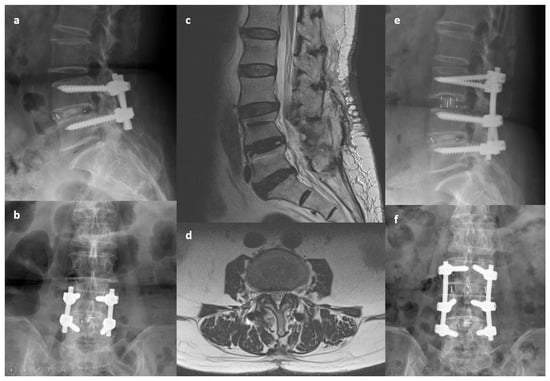

Figure 2.

An 81-year-old woman presented with low back pain, left thigh radiation, and claudication for 9 months. She had received transforaminal lumbar interbody fusion performed at the L4-5 segment 7 years previously for spondylolisthesis and spinal stenosis. (a,b) Preoperative X-ray images. (c,d) Preoperative MRI indicating central canal stenosis at L3-4. (e,f) Postoperative X-ray indicating oblique lumbar interbody fusion at L3-4 with extension of posterior instrumentation. The lower endplate of L3 may have been damaged during surgery.